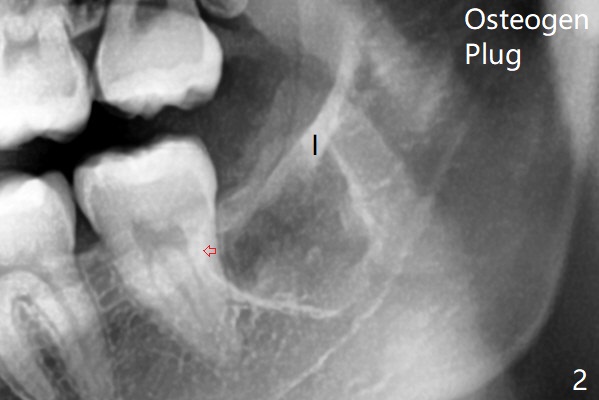

After extraction, one piece of Osteogen Plug is placed; the anterior end of the Internal Oblique Ridge (Fig.2 I) is located in the posterior of the socket.  As the socket heals, the anterior end of the ridge is expected to advance.